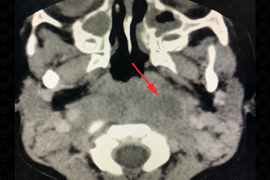

Texto alternativo para a imagem Figura 2. Créditos: Dra. Elazir Mota - Rio de Janeiro/RJ

Descrição das figuras 1 e 2: Evidenciando área hipodensa, sem realce pelo meio de contraste, mal definida, no espaço retrofaríngeo (setas vermelhas).

• Tomografia computadorizada do pescoço: Deve ser realizada, idealmente, com o uso do contraste venoso para identificar melhor a presença de coleções (figuras acima);